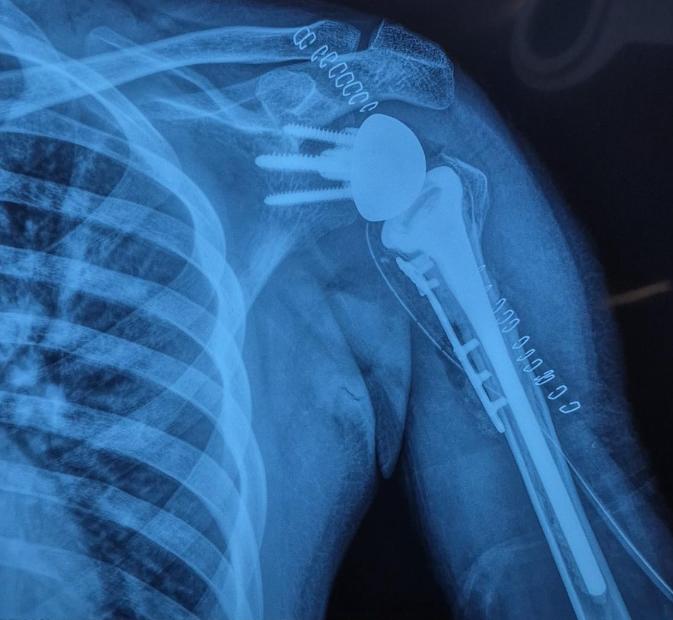

కిమ్స్ సన్షైన్ హాస్పిటల్లో వైద్యులు దక్షిణాఫ్రికాకు చెందిన 27 సంవత్సరాల యువకుడికి ప్రమాదంలో భుజం ఎముక విరిగిపోయి, భుజం కదపలేని పరిస్థితిలో బాధపడుతూ చికిత్స కోసం వచ్చిన యువకుడికి డోనర్ ఎముక గ్రాఫ్ట్ను ఉపయోగించి రివర్స్ షోల్డర్ రీప్లేస్మెంట్ శస్త్రచికిత్సను విజయవంతంగా నిర్వహించారు. దక్షిణ భారతదేశంలో ఈ అధునాతన భుజం మార్పిడి శస్త్రచికిత్స మొట్టమొదటిది.రోగి భుజం పైభాగపు చేతి ఎముక (ప్రాక్సిమల్ హ్యూమరస్) విరిగిపోవడం మరియు ఎముక పూర్తిగా దెబ్బతింది, దీంతో భుజం కలప లేని పరిస్థితి ఏర్పడింది. ఇటువంటి కేసులు ముఖ్యంగా యువ రోగులలో చికిత్స చేయడం చాలా క్లిష్టమైనది. సమగ్రంగా పరిశీలించిన అనంతరం, డాక్టర్ బి. చంద్రశేఖర్ నాయకత్వంలోని నిపుణులైన ఆర్థోపెడిక్ శస్త్రచికిత్స వైద్యుల బృందం, ప్రాక్సిమల్ హ్యూమరస్ అలోగ్రాఫ్ట్తో కలిపి రివర్స్ షోల్డర్ ఆర్థ్రోప్లాస్టీ చేయాలని నిర్ణయించారు – ఈ ప్రక్రియలో సర్టిఫైడ్ బోన్ బ్యాంక్ ద్వారా పొందిన డోనర్ ఎముక టిష్యూ ద్వారా దెబ్బతిన్న భాగాన్ని పున నిర్మించారు.షోల్డర్ రీప్లేస్మెంట్ లో ఈ ప్రక్రియ చ అరుదైనది మరియు అత్యంత క్లిష్టమైనది. నాలుగు గంటల పాటు జరిగిన శస్త్ర చికిత్స అనంతరం రోగి పూర్తిగా కోలుకున్నాడని డాక్టర్ చంద్రశేఖర్ తెలిపారు. రివర్స్ షోల్డర్ రీప్లేస్మెంట్ భుజం లో ఎముక లేదా కండరాలు బాగా దెబ్బతిన్నప్పుడు నొప్పిని తగ్గించి భుజం కదలికలను మెరుగుపరచడానికి షోల్డర్ రీప్లేస్మెంట్ ఎంతో ఉపయోగపడుతుందని కిమ్స్ సన్షైన్ హాస్పిటల్ షోల్డర్ సర్జరీ డైరెక్టర్ డాక్టర్ బి. చంద్రశేఖర్ తెలిపారు.